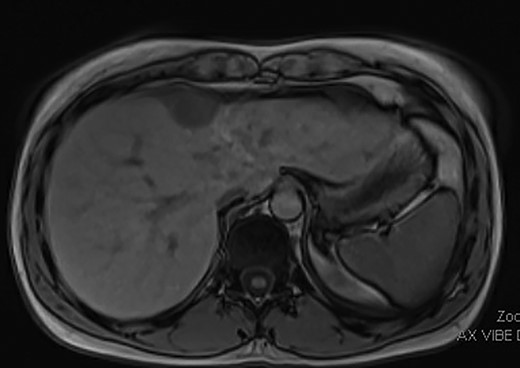

The patient is a previously healthy woman who presented at the age of 21 with severe abnormal uterine bleeding. She was initially treated with uterine artery embolization, and then underwent surgical resection in the form of a radical hysterectomy, right salpingectomy, left salpingo-oophorectomy and bilateral pelvic lymph node dissection. Pathology confirmed a 9 cm low-grade endometrial stromal sarcoma with right pelvic lymph nodes positive for metastasis, consistent with stage IIIC disease. She was also treated with long-term megestrol acetate. She developed recurrence adjacent to the right ovary in 2018 (at the age of 24), which was treated with surgical resection, doxorubicin, olaratumab and pelvic radiation therapy. She did well until early 2022, at the age of 28, when a surveillance abdominal magnetic resonance imaging (MRI) scan showed a lobulated enhancing mass measuring 3.6 × 2.4 cm over segment IVa of the liver, with possible parenchymal invasion (Fig. 1). The case was discussed between a hepatopancreatobiliary surgeon and gynecologic oncologist, and surgical resection was deemed to be a reasonable treatment strategy for this tumor.

Pre-operative MRI image showing a 3.6 × 2.4 cm mass over segment IVa of the liver with possible parenchymal invasion.